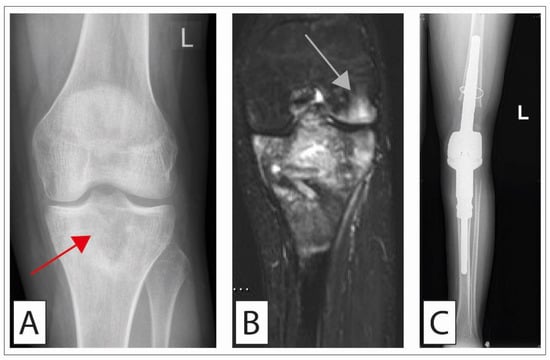

4. Chondrosarcoma

4.2. Therapy

4.2.2. Surgical Treatment

4.2.3. Surgical Treatment of Chondrosarcoma of the Pelvis